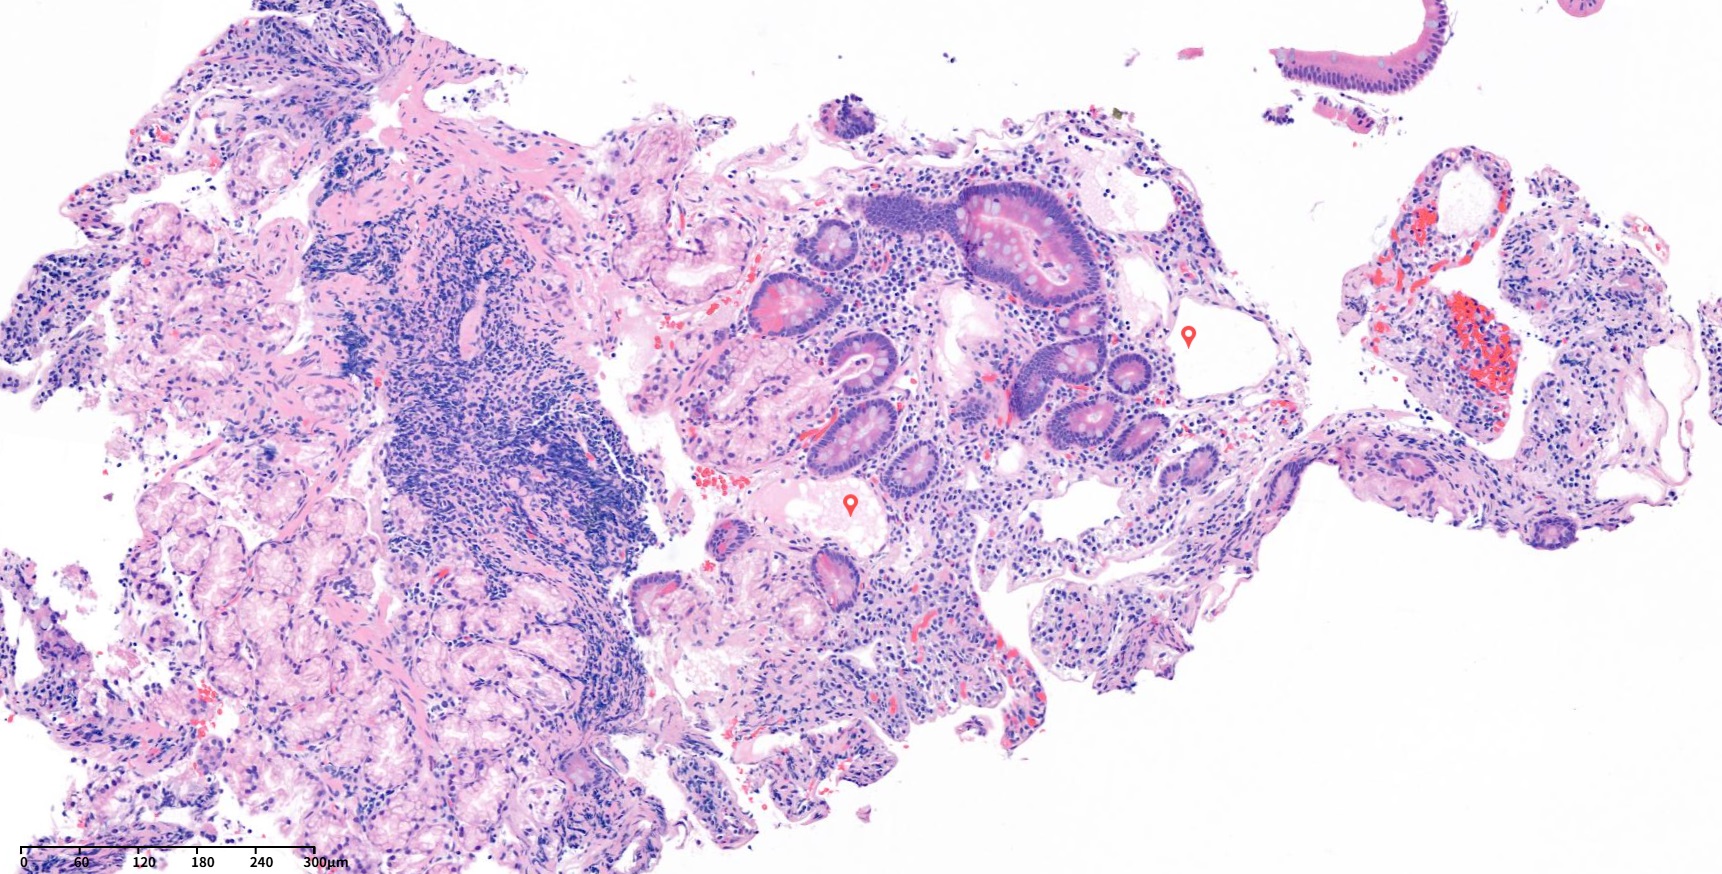

Terminal illiumÀÇ Á¶Á÷»çÁøÀÔ´Ï´Ù. Àú¹èÀ²·Î º¸¸é Ç÷°üÀÇ »óÇǼ¼Æ÷À̰í À̰ÍÀÌ lymphatics ÀÔ´Ï´Ù. ÁÖº¯Àº lamina propria ÀÔ´Ï´Ù. Á»´õ °í¹èÀ²¿¡¼­ º¸¸é ´ÙÀ½°ú °°ÀÌ vascular structure°¡ º¸À̴µ¥ ÀÌ´Â Á¤»óÁ¶Á÷¿¡¼­´Â º¸ÀÌÁö ¾Ê´Â ´Ã¾î³­ lymphatics ÀÔ´Ï´Ù. ±×¸®°í lamina propria¿¡ cytoplasmÀÌ ¸¹°í ºÒÅõ¸íÇÑ lipid-laden macrophage°¡ ¹¶ÃÄÀִµ¥ ÀÌ´Â xanthomaÀÔ´Ï´Ù. D2-40´Â lymphaticsÀÇ endothelial cell¿¡ ¹ÝÀÀÇÏ´Â markerÀÔ´Ï´Ù. º¸½Ã´Â °Íó·³ ´Ã¾î³­ lympaticsÀ» È®ÀÎ ÇÒ ¼ö ÀÖ½À´Ï´Ù. CD68Àº macrophage ¸¶Ä¿Àε¥ lympatics¿¡¼­ leakageµÈ lipid¸¦ ó¸®Çϱâ À§ÇØ ¸ð¿©µç macrophage°¡ °¥»öÀ¸·Î ¿°»öµÇ´Â °ÍÀ» È®ÀÎ ÇÒ ¼ö ÀÖ¾ú°í ÀÌ¿Í °°Àº ¼Ò°ßÀº lymphangiectasiaÀÇ Æ¯ÀÌÀû Á¶Á÷ÇÐÀû ¼Ò°ßÀÔ´Ï´Ù.